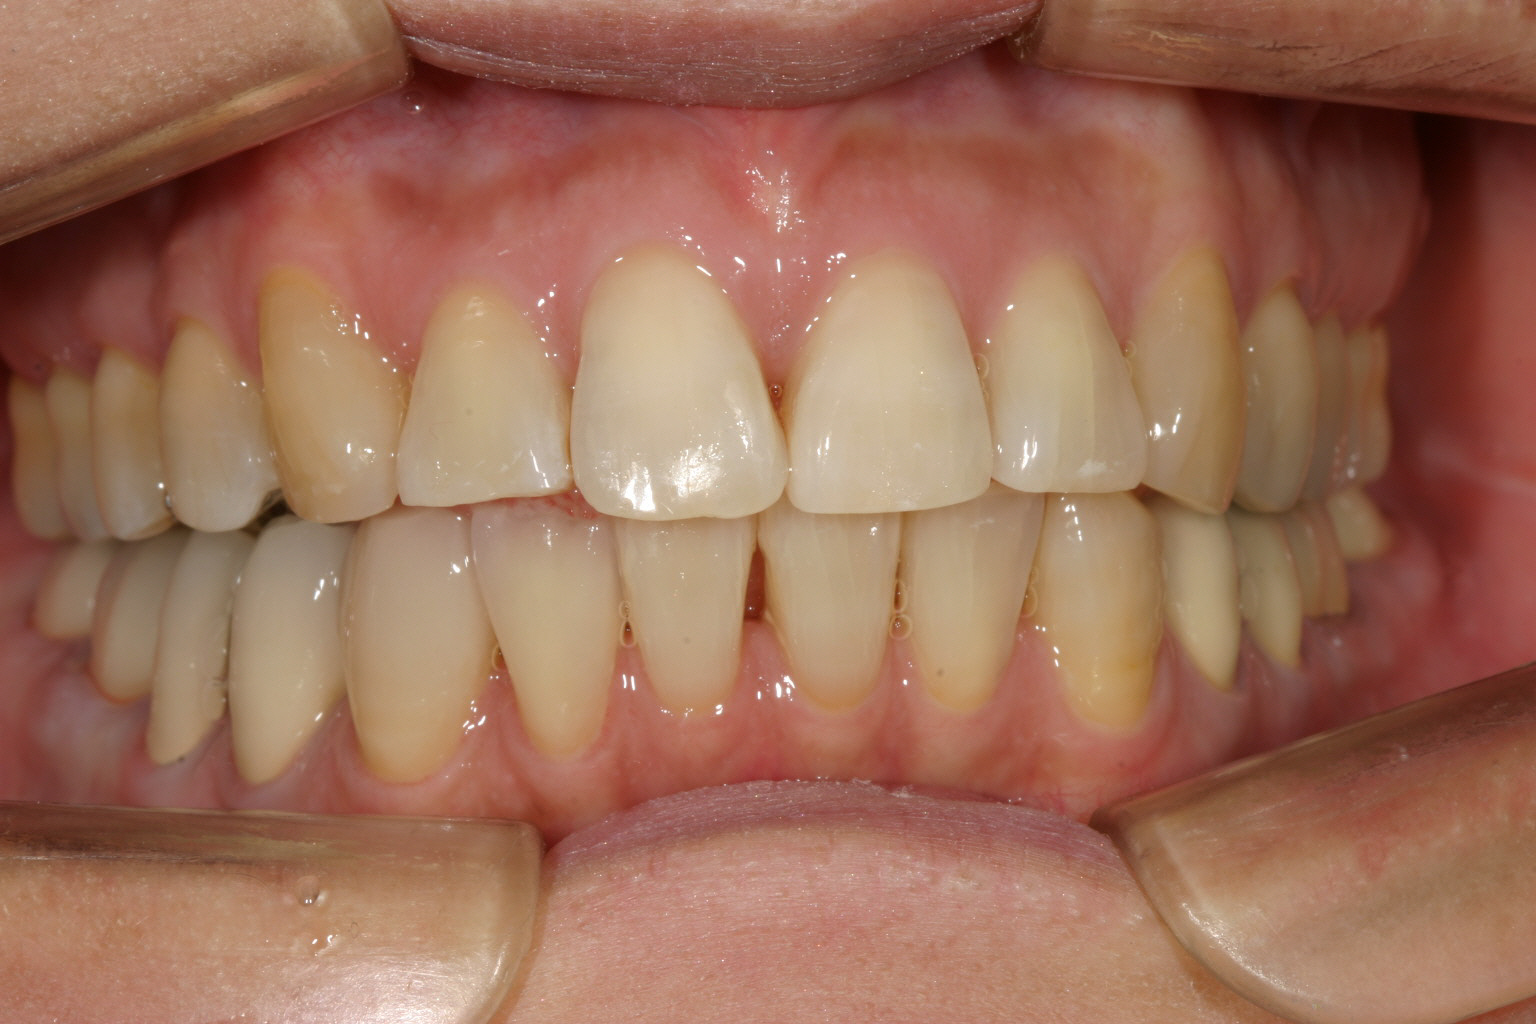

側面観はオーバージェットも改善してます。

綺麗に並びました。

綺麗に咬合してます。 最初の正面観見て頂ければ正中が左にシフトし改善しているのが分かります。

こちらの症例は顎偏(顎偏移)に伴う顎関節症の治療例です、この様に誤った臼歯部冠補綴による顎関節症はよく見られます。

この様に補綴が原因であればその原因となる補綴物を入れ替える事で簡単に顎位の変更が出来、その後マルチループワイヤーで噛み合わせ修正しました。

と言う事で顎関節症は顎位改善により完治致しました。